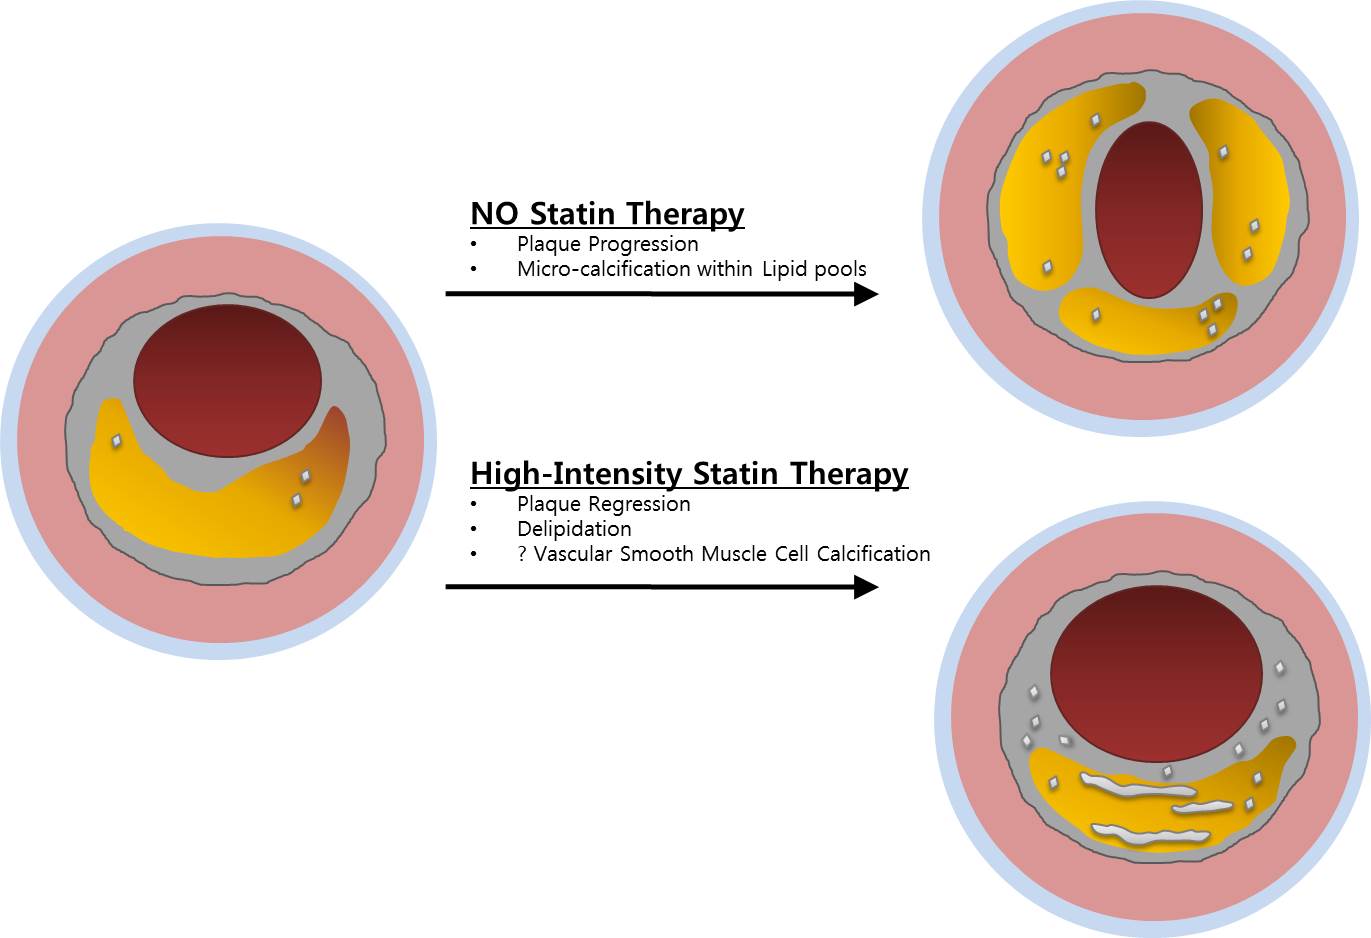

스타틴의 부작용으로는 근육통, 근력 약화, 간 기능 장애, 인지 기능 저하 등이 있으나 실제 임상 경험상 드물고 자가면역 혈관 질환(예: 타우, 동맥염 또는 가와사키병)과 관련이 있는 경우는 드물다. 신장이 제대로 기능하지 않는 경우 지연이나 검사가 필요하지 않을 수 있습니다. 흉통을 인지하고 적절한 치료를 받으면 관상동맥 질환의 위험을 줄일 수 있습니다. 광범위한 손상은 심각한 응급 상황과 만성 심부전으로 이어질 수 있으며, 이는 심장 기능 저하, 고콜레스테롤 및 스타틴 부작용으로 이어집니다. 협심증의 증상은 특히 흉골 전면 바로 아래의 가슴에 압박감, 조임 및 통증이 있습니다. YouTube를 서핑하고 일부를 본 다음 인터넷 검색에 어려움을 겪고 있습니다. 결국 어디 가서 정보를 수집하고 모두가 유명하다는 등 너무 많은 것을 추천합니까? 심장기능, 혈관질환, 석회화, 정도 등을 미리 예측할 수 있습니다. 관상동맥 석회화의 정도는 정상이고 일정 범위를 갖지만 경증, 중증, 중등도 및 고도의 관상동맥 석회화로 나눌 수 있습니다. 손상이 광범위하면 매우 위험한 응급 상황이 될 수 있으며 장기간 반복되면 심부전 및 심장 기능 저하로 이어질 수 있습니다. 수술적 합병증이 있을 수 있으나 심각한 기저질환이 없는 대부분의 환자에게 관상동맥우회술의 위험성은 약물복용 중 안전한 회복과 퇴원이다. 연구팀은 공복혈당과 당화혈색소에 따른 관상동맥석회화 위험도를 발표한 최인영 교수와 장유수 교수의 연구에서 관상동맥 석회화 위험이 1명에서도 증가했다. 당뇨병 이전 수준. 연민 이 상태에 있다면 건강한 생활 방식과 혈압, 혈당 및 콜레스테롤 수치 상승을 방지하는 방법을 실천하십시오. 유투브도 돌아다니고 영상도 보고 웹서핑도 하고. 결국, 모두가 마음으로 정보를 수집하고 유명하든 아니든 너무 많이 추천하고 싶다면 어디로 가야합니까?